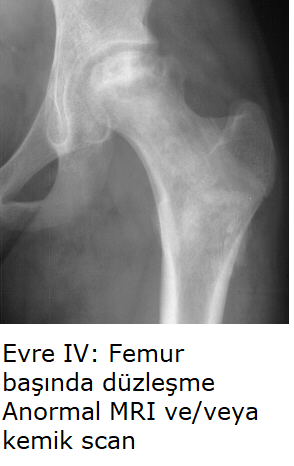

Evre IV: Eklem aralığında daralma, ileri osteoartrit. Terminal safha.

C. Kırmızı Bölge (Post-Collapse / Mekanik İflas - Evre III/IV)

Profil: Crescent Sign (+), çökme gerçekleşmiş. Tutulum >%50.

Strateji (Rekonstrüktif): Genç hastalarda yükü kaydırmak için Osteotomi; ileri evrede Total Kalça Artroplastisi (THA - Kalça Protezi). Cerrahi sonrası diğer kalçayı korumak için profilaktik protokol başlatılır.